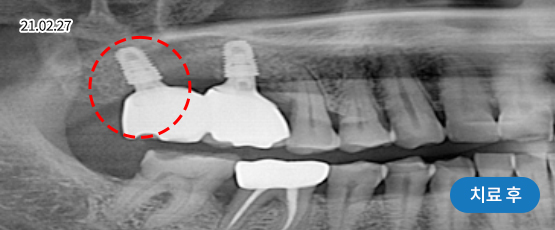

임플란트 재수술

처음보다 더 어렵고 까다로운 재수술 임플란트

잘못된 임플란트 수술과 잘못된 임플란트 관리는 부작용을 발생시킬 수 있으며, 통증을 동반하게 됩니다.

임플란트 재수술은 기존 임플란트를 제거 후 새롭게 잇몸뼈를 만들고 알맞은 잇몸형태를 잡아내어 새 임플란트를 식립하는 시술입니다.

재수술이 필요한 대상

임플란트 주위염으로 인해 잇몸뼈가 녹은 경우

임플란트를 제대로 식립하지 못한 경우

오래된 임플란트가 흔들리는 경우

임플란트가 서로 너무 가깝게 심어져 염증이 생긴 경우